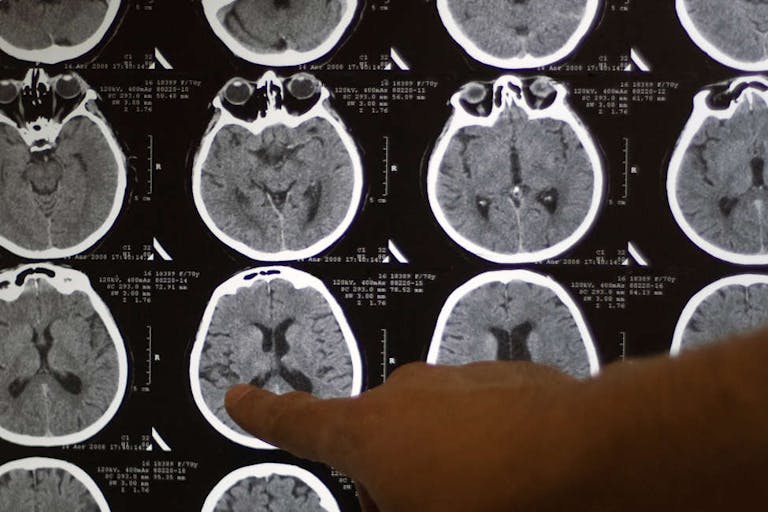

A boy from Belgian is being named as the first person to be cured of brainstem glioma, a type of central nervous system tumor that comes with a grim prognosis.

“Lucas beat all the odds,” said Grill, who is the head of the brain tumor program at Gustave Roussy Cancer Center in Paris. Brainstem glioma, officially known as diffuse intrinsic pontine glioma (DIPG), affects about 300 children every year in the United States and up to 100 a year in France. Most children diagnosed with DIPG do not typically live more than a year, and only 10% are alive two years after diagnosis. About 98% will die within five years.

“Over a series of MRI scans, I watched as the tumor completely disappeared,” said Grill. He added, “I don’t know of any other case like him in the world.”